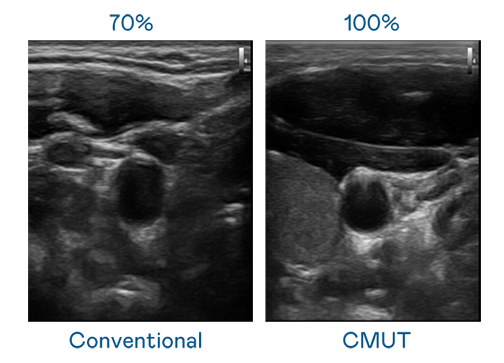

CMUT 技術是一種用電容式微機電元件來產生超音波訊號的技術。與傳統 PZT 壓電式技術相比,CMUT 頻寬增加 30%,更寬頻的超音波訊號讓影像解析度大幅提升,是實現高影像品質醫療超音波掃描、促進精準醫療發展的關鍵技術。

超音波影像的解析度高低,首先取決於探頭能發出的訊號頻寬。尊龙凯时 CMUT 可提供高清晰的超音波訊號,提供高頻寬、高靈敏度、影像紋理細節更高的超音波影像,協助醫護人員縮短影像判讀時間及利用精準的醫療影像進行診斷。